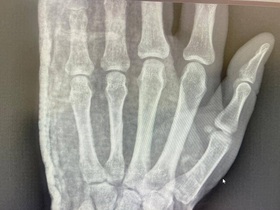

- діагностика: КТ, МРТ, рентгенографія, діагностична артроскопія;

Травматологи центру МЕДІКОМ в м. Київ для уточнення місцезнаходження пошкоджень і їх тяжкості проводять такі інструментальні дослідження: